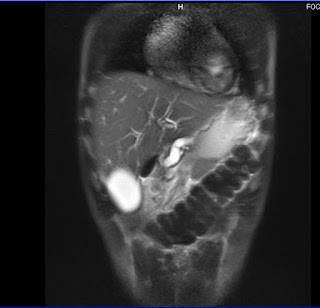

USG Abdomen

Acute pancreatitis secondary to chronic cholelithiasis